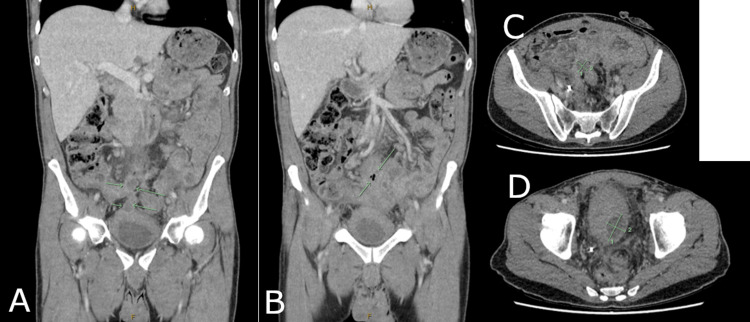

免疫治疗开始四个月后,患者出现高热及盆腔疼痛,复查CT显示原肿瘤区域新发多房性盆腔脓肿,伴广泛炎性改变及气液平面(图5)。患者随即入院,接受影像引导下脓肿引流及抗生素治疗。住院期间患者整体情况有所改善,但因盆腔感染持续存在,免疫治疗暂时中断。

图5. CT影像冠状位(A、B)与轴位(C、D)扫描所示盆腔脓肿